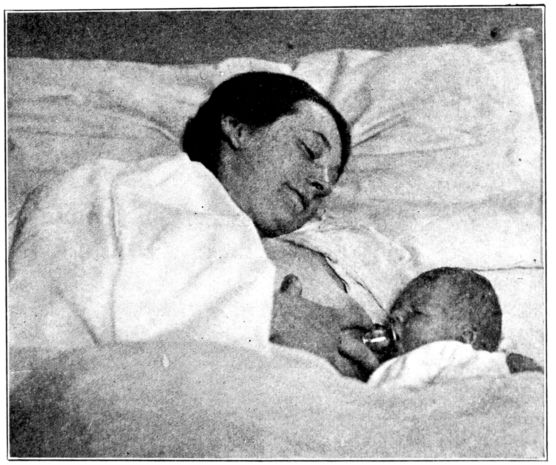

| 138. | Position of mother and baby for nursing in bed | 359 |